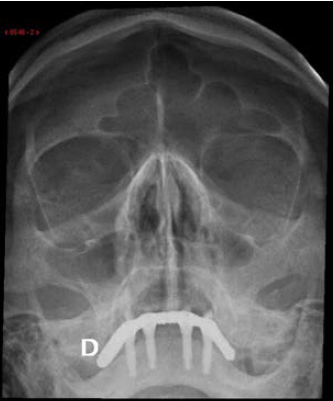

Uma paciente de 60 anos realizou radiografia de seios da face com queixa de cefaleia. Frente às imagens, considera-se que há: